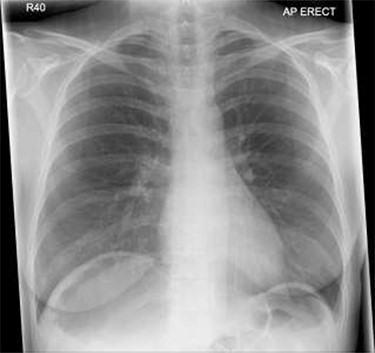

Patient initially diagnosed as biliary colic and surgical team had been contacted. Plain Abdominal radiograph showed dilated small bowels loops (Fig. 1). Chest radiograph revealed air under right hemi-diaphragm (Fig. 2). CT scan was done in emergency department and confirmed interposition of bowel between the diaphragm and the liver with a vascular/mesenteric pedicle swirl suggestive of malrotation or volvulus of the right colon. There was marked mural thickening and bold dilatation with high attenuation mucosa in keeping with closed loop obstruction and possible necrosis (Figs 3 and 4).

Although an abdominal X-ray can be helpful in terms of diagnosis but not in all conditions, CT scan is an investigation of choice for such cases of caecal volvulus to make solid diagnosis and operate based on that evidence. In our patient the caecum, ileum and ascending colon were found entrapped and twisted at right hepato-diaphragmatic space resulting in an unusual Chilaiditi syndrome; hence a chest X-ray may give false impression of bowel perforation. Therefore, clinical correlation is always mandatory in order to consider different management options as in such cases.